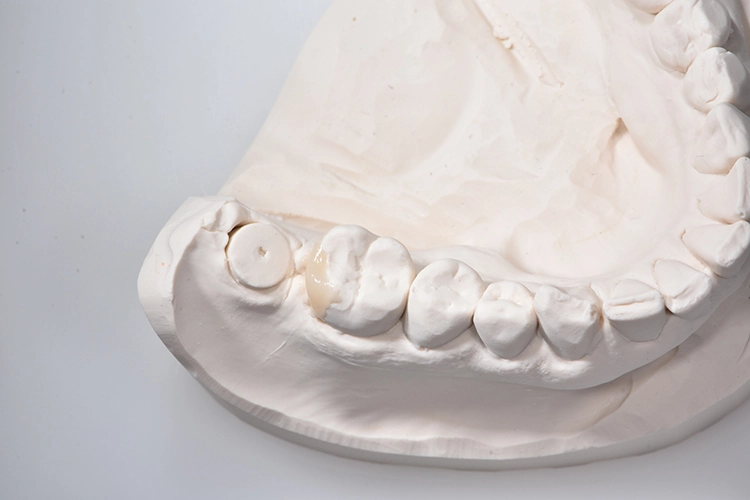

Bilder: Dr. Lampson / HannkerAbb. 2a: Gipsmodelle. Bei Zahn 46 wurde Wachs hinzugefügt, um die Form im distalen Bereich zu verbessern.

Bilder: Dr. Lampson / HannkerNach dem Ausgießen der Abformung sowie dem Scan des Gips- und Antagonistenmodells (Abb. 11a bis d) folgten das Kronendesign und die Fräsparametereinstellung per CAD/CAM-Programm (PowerMill Pro, Autodesk) (Abb. 12). Hergestellt wurden die Kronen aus Lithium-Disilikat-CAD/CAM-Blöcken (InitialTM LiSi Block, Farbe A2) (Abb. 13), die sich insbesondere durch eine hohe Opaleszenz bei hochtransluzenten (HT) Farbtönen auszeichnen und so auch ohne weitere Charakterisierung hochästhetische Ergebnisse erzielen.

Bilder: Dr. Lampson / HannkerNach 35-minütigem Schleifen (Exocad PowerMill CAM, DMG) wurde die Restauration aus dem Block entfernt und der Bereich der Anstiftung geglättet. Anschließend galt es, die Kronen auf den jeweiligen Formen und am Modell zu prüfen, wobei sich bereits eine perfekte Randpassung zeigte (Abb. 14 und 15). Danach erfolgte die Glaslötung der Implantatkrone auf das individuell angepasste Zirkonoxid-Abutment (Abb. 16).